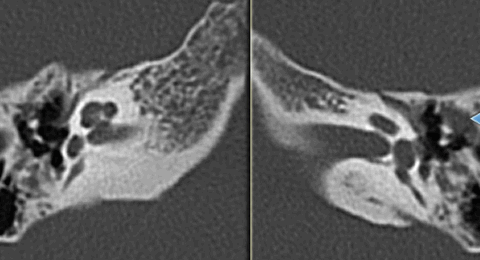

Холестеатома аттика (перфорация ненатянутой части перепонки): КТ в А. Аксиальной и Б. коронарной проекции.

Передняя часть латеральной стенки аттика разрушена мягкотканым массивом, распространяющимся латерально к косточкам,

которые частично разрушены и смещены в медиальном направлении. Холестеатома при перфорации в натянутой части: А. Аксиальная и Б. Коронарная проекции КТ.

Задняя часть латеральной стенки аттика разрушена мягкотканым массивом, заполняющим задневерхний квадрант барабанной полости и заднюю часть аттика.

Холестеатома расширяет aditus и проникает в antrum, который выглядит увеличенным вследствии эрозии периантральных клеток. А. Коронарные и Б. Аксиальные КТ.